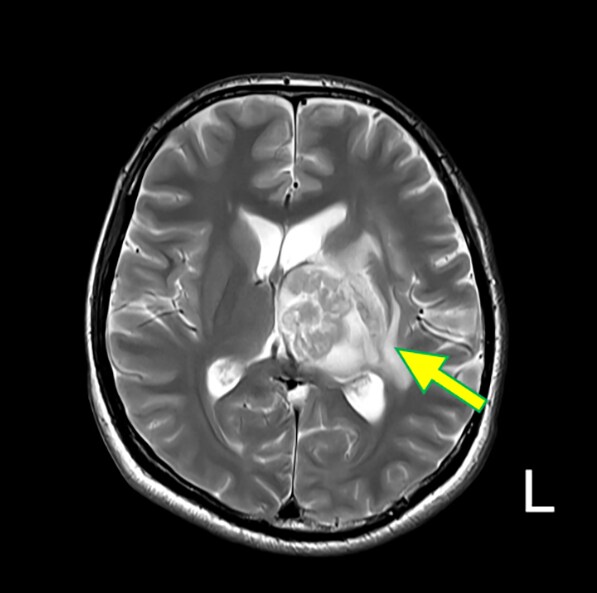

図2.T2WI (Tra.)

比較的整な辺縁を持つ嚢胞の内部に、不整形の実質構造を認める(矢印)。第3脳室は圧排され閉鎖している。周辺浮腫を伴っている。